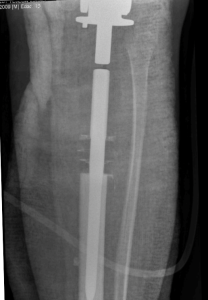

🏥 Cirugía Oncológica en Paciente Pediátrico en el HMyN Read More »